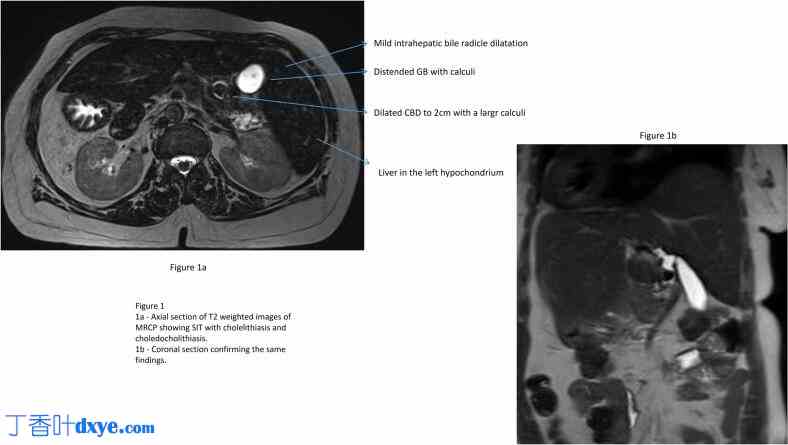

腹部超声显示左季肋部和上腹部肝脏回声正常,无局灶性病变,胆囊结石 1 cm,壁厚正常,超声墨菲征阳性。由于肠道气体过多,胆总管无法显影。MRCP 显示内脏反位特征,胆囊扩张,1.5 cm 大结石,胆总管扩张 2 cm,胆总管中部结石 1.8 cm,肝内胆管根扩张(图 1)。她最终被诊断为完全内脏反位、胆囊结石和胆总管结石,并伴有胆管炎阻塞性黄疸。鉴于胆管炎,她接受了肠外抗生素治疗,并计划进行 ERC、取石和胆道支架置入术。然而,由于十二指肠解剖结构改变和操作困难,她曾两次尝试ERC,均失败。随后,她被转诊至作者的外科胃肠病学团队,并决定进行手术干预。

MRCP轴向和冠状切面显示胆结石和胆总管结石的内脏反位。